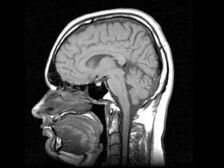

снимка от открити източници

Новосибирските учени са разработили лекарство, което прави човешкият мозък да произвежда стволови клетки, необходими за възстановяване на болни органи. „Лекарството се отнася до регенеративно и няма аналози в света. Започваме тази година клинични изпитвания, предклинични изпитвания, които сме завършили, “- каза председателят на съвета и съсобственик на дружеството, разработил лекарството, Андрей Артамонов. Според него лекарството кара мозъка на възрастните да произвежда нов стволови клетки, които по-късно откриват увреден орган и възстанови го. „При децата мозъкът активно произвежда ствол клетки, защото бебето расте. И мозъкът на възрастен способен да ги произвежда, само той не иска да го прави – на него няма нужда. Нашето лекарство стимулира производството на собствено стъбло клетки “, обясни Артамонов. Според него всички операции с стволови клетки сега се произвеждат извън човешкото тяло, които носи определен риск, свързан с факта, че модифицирана, изкуствено размножена клетка може да започне взаимодействат на неочаквано място. Клетките могат да бъдат въведени, но това винаги е риск, защото не е много ясно къде се намират диференцирани. Въпреки че са ваши, те се разпространяват извън вашия тяло. Собствените стволови клетки не могат да се провалят там диференцират. Намират повреден орган и започват това възстановете тялото “, добави Артамонов. Клинични изпитвания наркотикът ще продължи година и половина, съобщава Интерфакс.